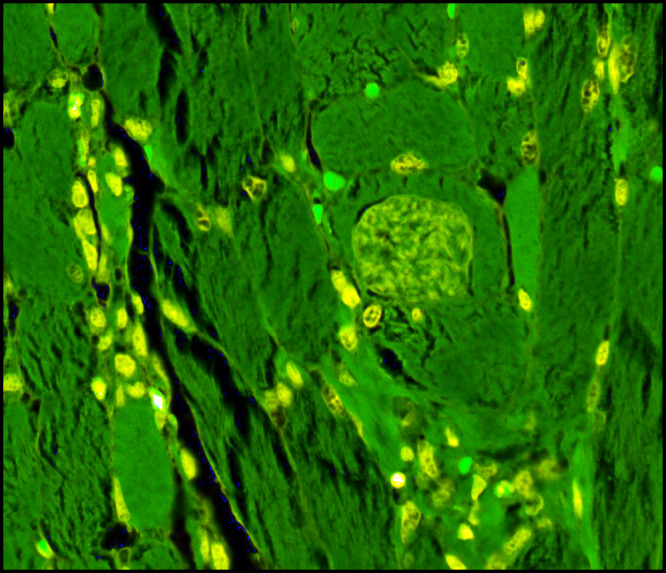

Sarcocystis in Domestic Rabbits

What is Sarcocystis? Sarcocystis is a genus of single-celled parasites with a complex lifecycle involving... Read more.